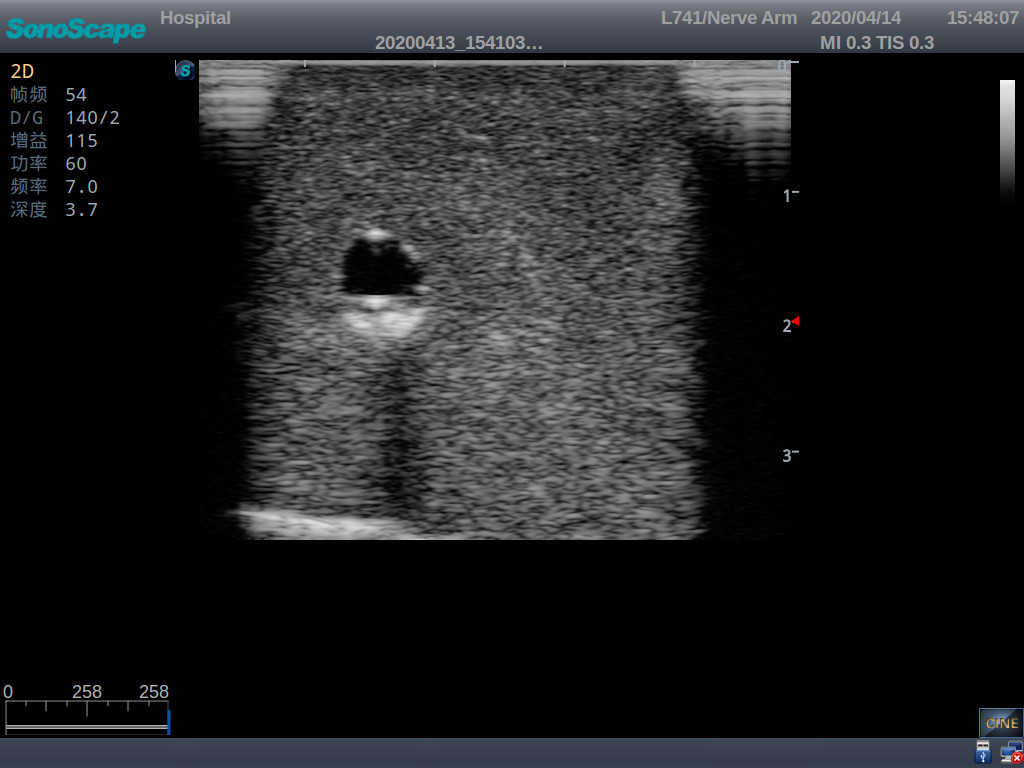

2) It can be used by real ultrasound machines

3) Clear and real images of the tissues and organs (basilic vein and superior vena cava)

4) When conducting vascular puncture, the piercing can be truly felt, and venous blood outflow can be seen

6) Detect whether the catheter is properly placed